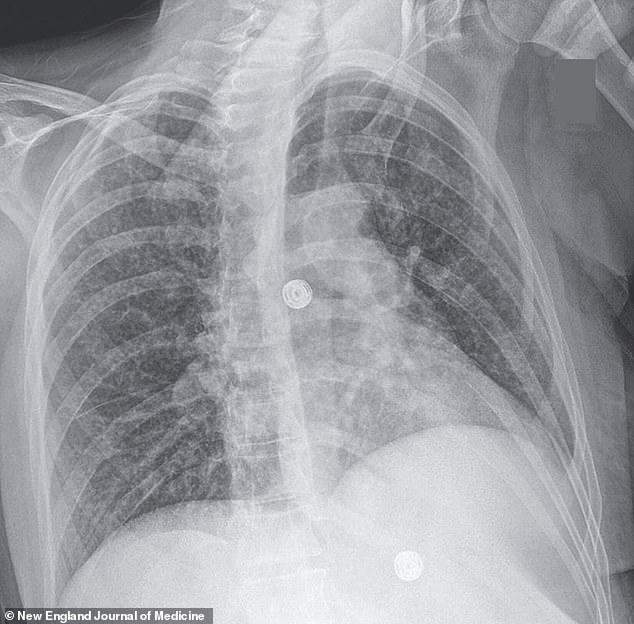

The above x-ray scan shows nodules in the woman’s lungs from tuberculosis